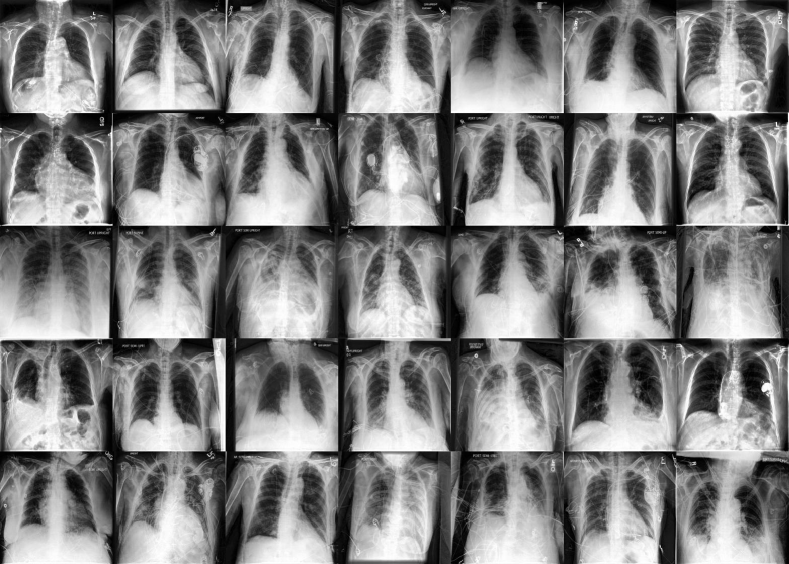

The first setting that we consider is histopathology. Different staining procedures followed by different hospitals lead to distribution shifts that can challenge a machine learning model that has only encountered images from a particular hospital. The CAMELYON17 challenge by Bandi et al. (2018) aims to improve generalization capabilities of automated solutions and reduce the workload on pathologists that have to manually label those cases. The corresponding dataset contains whole-slide images from five different hospitals and the task is to predict whether the histological lymph node sections captured by the images contain cancerous cells, indicating breast cancer metastases. Two of the hospital datasets provided by the challenge are held-out for out-of-distribution evaluation and three are considered in-distribution, because they use similar staining procedures. We consider this as the simplest setting for our experiments, because there are no extreme prevalence or demographic shifts. Additionally, the considered image resolution (96×96969696\times 96) is smaller in comparison to the imaging modalities presented later, which allows generation directly at that resolution without requiring an upsampler. The labelled dataset contains 455,954455954455,954 images, while the unlabelled dataset contains 1.81.81.8 million images from the three training hospitals; full statistics are given in Table A1. The unlabelled dataset does contain the hospital identifier, but not the diagnostic label.

In order to understand the impact of the number of labelled examples on fairness and overall performance, we create different variants of the labelled training set, where we vary the number of samples from two of the three training hospitals (3 and 4). The number of labelled examples from one hospital remains constant. For each setting, we train a diffusion model using the labelled and unlabelled dataset (using only the diagnostic label whenever available in one case, and the diagnostic label together with the hospital id in the other case). We, subsequently, sample synthetic samples from the diffusion model and train a downstream classifier that we evaluate on the held out in- and out-of-distribution datasets (results shown in Figure 3). We compare top-level classification accuracy and fairness gap, i.e. best-to-worst accuracy gap between the in-distribution hospitals to different baselines (more details about baselines are provided in subsection E.2). We find that using synthetic data outperforms both baselines in-distribution in the less skewed (with 1000 labelled samples from hospitals 3, 4) and more skewed setting (with only 100 labelled samples) while closing the performance gap between hospitals. We obtain the best accuracy out-of-distribution when using all in-distribution labelled examples as shown in Figure 3b (in the OOD setting there is one validation and one test hospital so we do not report a performance gap). We find that performing color augmentation on top of the generated samples generalizes best overall, leading to a 7.7%percent7.77.7\% absolute improvement over the baseline model on the test hospital. This validates that indeed we can use synthetic data to better model the data distribution and outperform variants using real data alone. We also observe that this method is most effective in the low-data regime (i.e. more skewed setting in Figure 3a). In Figure G1 we show some examples of healthy and abnormal histopathology images generated at 96×96969696\times 96 resolution.